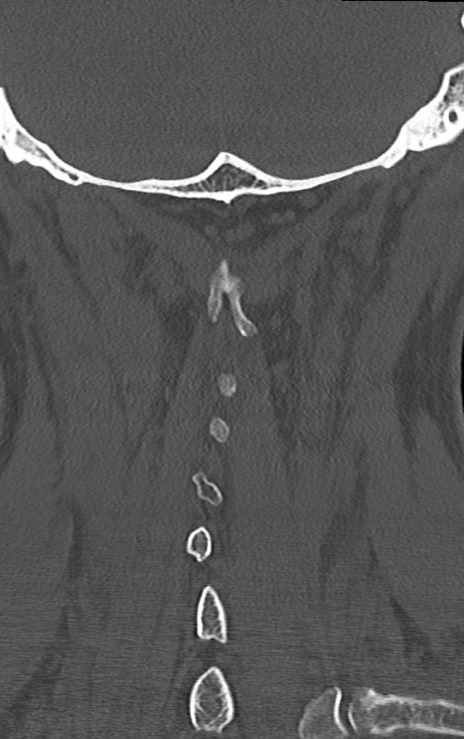

頚椎CT

矢状断像